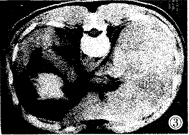

图1 平扫肝右叶有一肝癌结节,边界模糊

, http://www.100md.com

图2 增强后病变范围明显缩小

图3 同一病人术后标本作免疫组化微血管染色,发现癌边缘区有十分丰 富的微血管(×200)